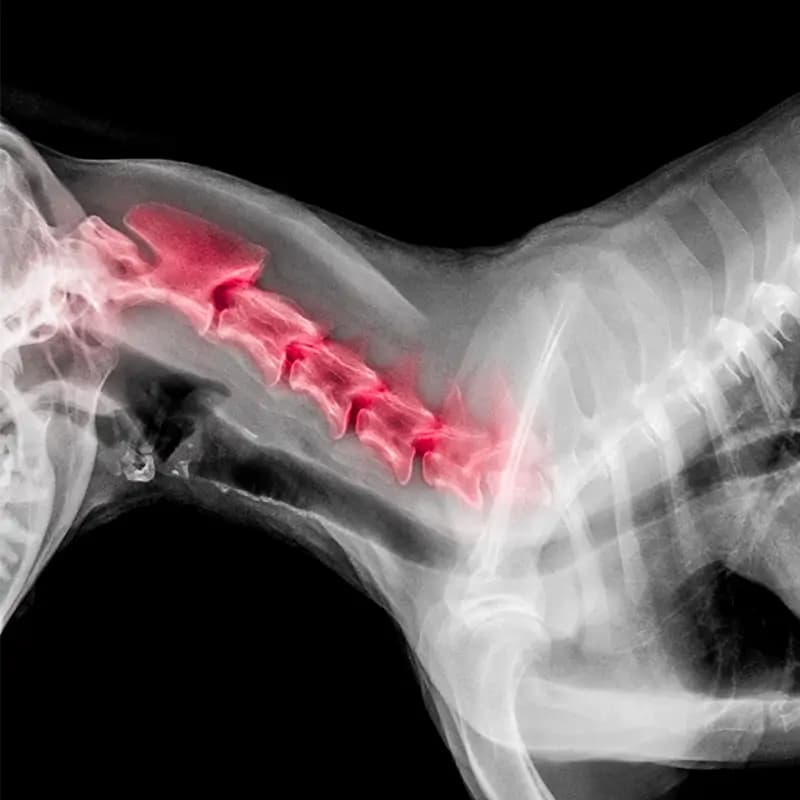

Anatomie & Fysiologie

Pathologie